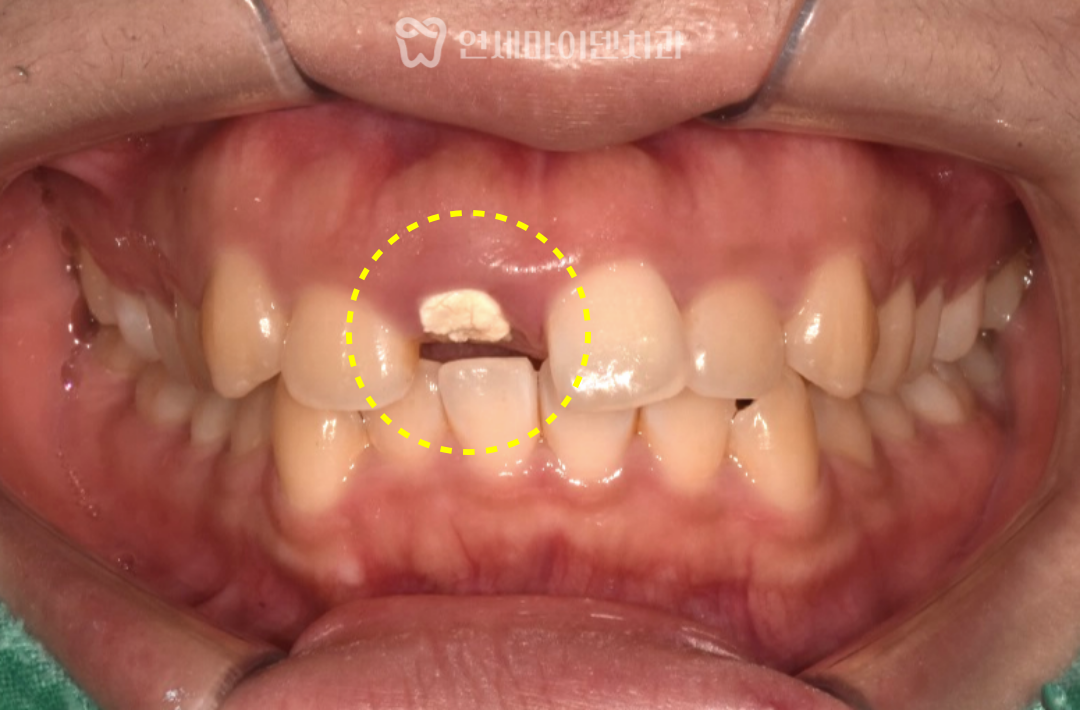

내원 당시 치아는 잇몸 라인과

거의 동일한 위치에서 깨져 있었습니다.

치아가 사라진 자리는 잇몸이 차올라 있고,

잇몸 레벨도 양쪽과 다르게 틀어져 있었습니다.

하지만 치아가 드러나면서

잇몸 레벨의 비대칭이 남아 있었기 때문에,